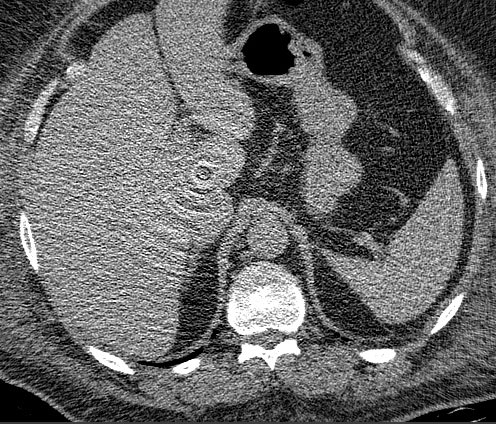

环形伪影校正(Ring Artifact Correction)

原理:探测器元素的故障或校准误差会导致在重建图像中出现以扫描中心为圆心的同心圆环。这是因为每个探测器元素在扫描过程中旋转一周,其故障会在重建图像中形成圆环。

CT环形伪影示例CT环形伪影:由探测器元素故障或校准误差导致的同心圆环伪影,以扫描中心为圆心

环形伪影的特征

• 位置固定:以扫描中心为圆心的同心圆环,在所有层面上位置相同

• 密度表现:通常表现为高密度环(故障元素信号过高)或低密度环(故障元素信号过低)